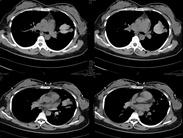

小兒真菌性肺炎

• 小兒真菌性肺炎

628健康網為您分享有關小兒真菌性肺炎的癥狀,小兒真菌性肺炎的治療方法,小兒真菌性肺炎的預防知識,小兒真菌性肺炎的癥狀...